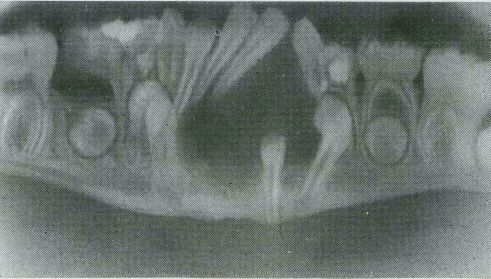

Одонтома нижней челюсти: фотографии и медицинская информация